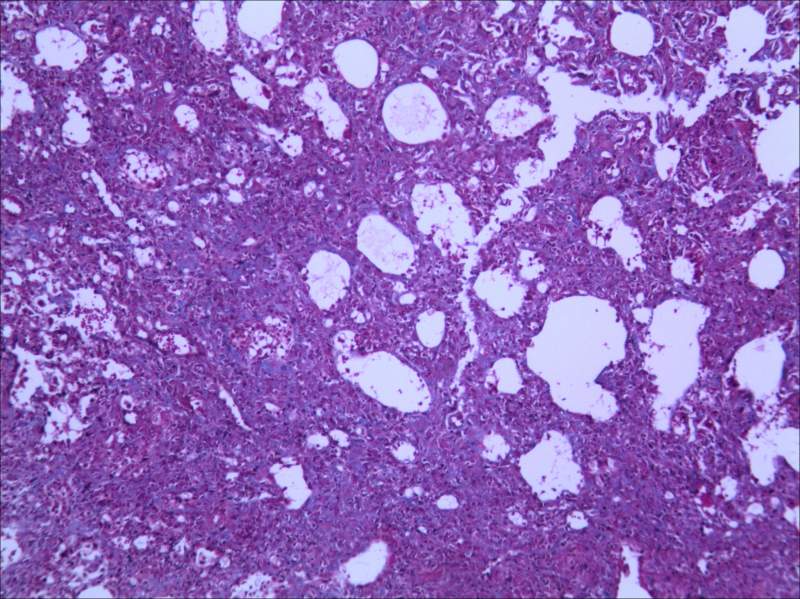

RT£¬ÇóÖú¸ßÈËÖ¸µãÒ»¶þ¡£¡£ÓÃImage J´¦ÀíÂíËÉȾɫÇÐÆ¬Á÷³Ì¡£¡£ ÉÏ´«2ÕÅͼ¡£¡£¡£Çó¾ßÌå½Ì³Ì M10-2-X+++-Y+++.JPG M40-2-X+++-Y+++.JPG |

ÎÒû×ö¹ý£¬µ«ÊǰïÎÒʦ½ã´ò¹ýÏÂÊÖ£¬Ï£Íû¶ÔÄãÓаïÖú°É¡£´ó¸Å²Ù×÷Á÷³ÌÈçÏ 1£®ÍÑÀ¯ £¨1£©½þÅݶþ¼×±½10min£¬½þÅݶþ¼×±½5min£¬½þÅݶþ¼×±½5min£¬½þÅÝ100%¾Æ¾«2min£¬95%¾Æ¾«2min£¬75%¾Æ¾«2min£¬Ë®³åÏ´¸É¾»¡£ 2.Ⱦɫ °ÚºÃƬ×Ó£¬ËÕÄ¾ËØ¼×Òº£ºËÕÄ¾ËØÒÒÒº=1:1Ⱦɫ 5min£¬³åϴȾҺ£¬·ÅÈë¼Ü×Ó£¬Ï¡ÑÎËáպһϣ¬³åÏ´5min£¬°ÚºÃƬ×Ó£¬²Á¸ÉË®£¬¼Ó Àö´ººìËáÐÔÆ·ºìҺȾ7·ÖÖÓ£¬×ÔÀ´Ë®³åÏ´5min£¬ 1%Á×îâËáË®ÈÜÒº´¦ÀíÔ¼5·ÖÖÓ£¬µ¹µôÁ×îâËᣬ²»ÓÃˮϴ£¬Ö±½Ó¼Ó2%±ù´×ËáÊÊÁ¿´¦Àí1·ÖÖÓ£¬×ÔÀ´Ë®³åÏ´5min£¬ÓÃÖÐÐÔÊ÷Ö¬·âƬ¡£ |